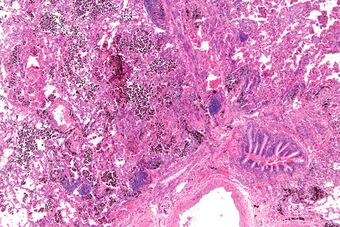

Micrograph showing a pulmonary hemorrhage. H&E stain.

Pulmonary hemorrhage (or pulmonary haemorrhage) is an acute bleeding from the lung, from the upper respiratory tract and the trachea, and the pulmonary alveoli. When evident clinically, the condition is usually massive.[1] The onset of pulmonary hemorrhage is characterized by a cough productive of blood (hemoptysis) and worsening of oxygenation leading to cyanosis.[1] Treatment should be immediate and should include tracheal suction, oxygen, positive pressure ventilation, and correction of underlying abnormalities such as disorders of coagulation. A blood transfusion may be necessary.[1]